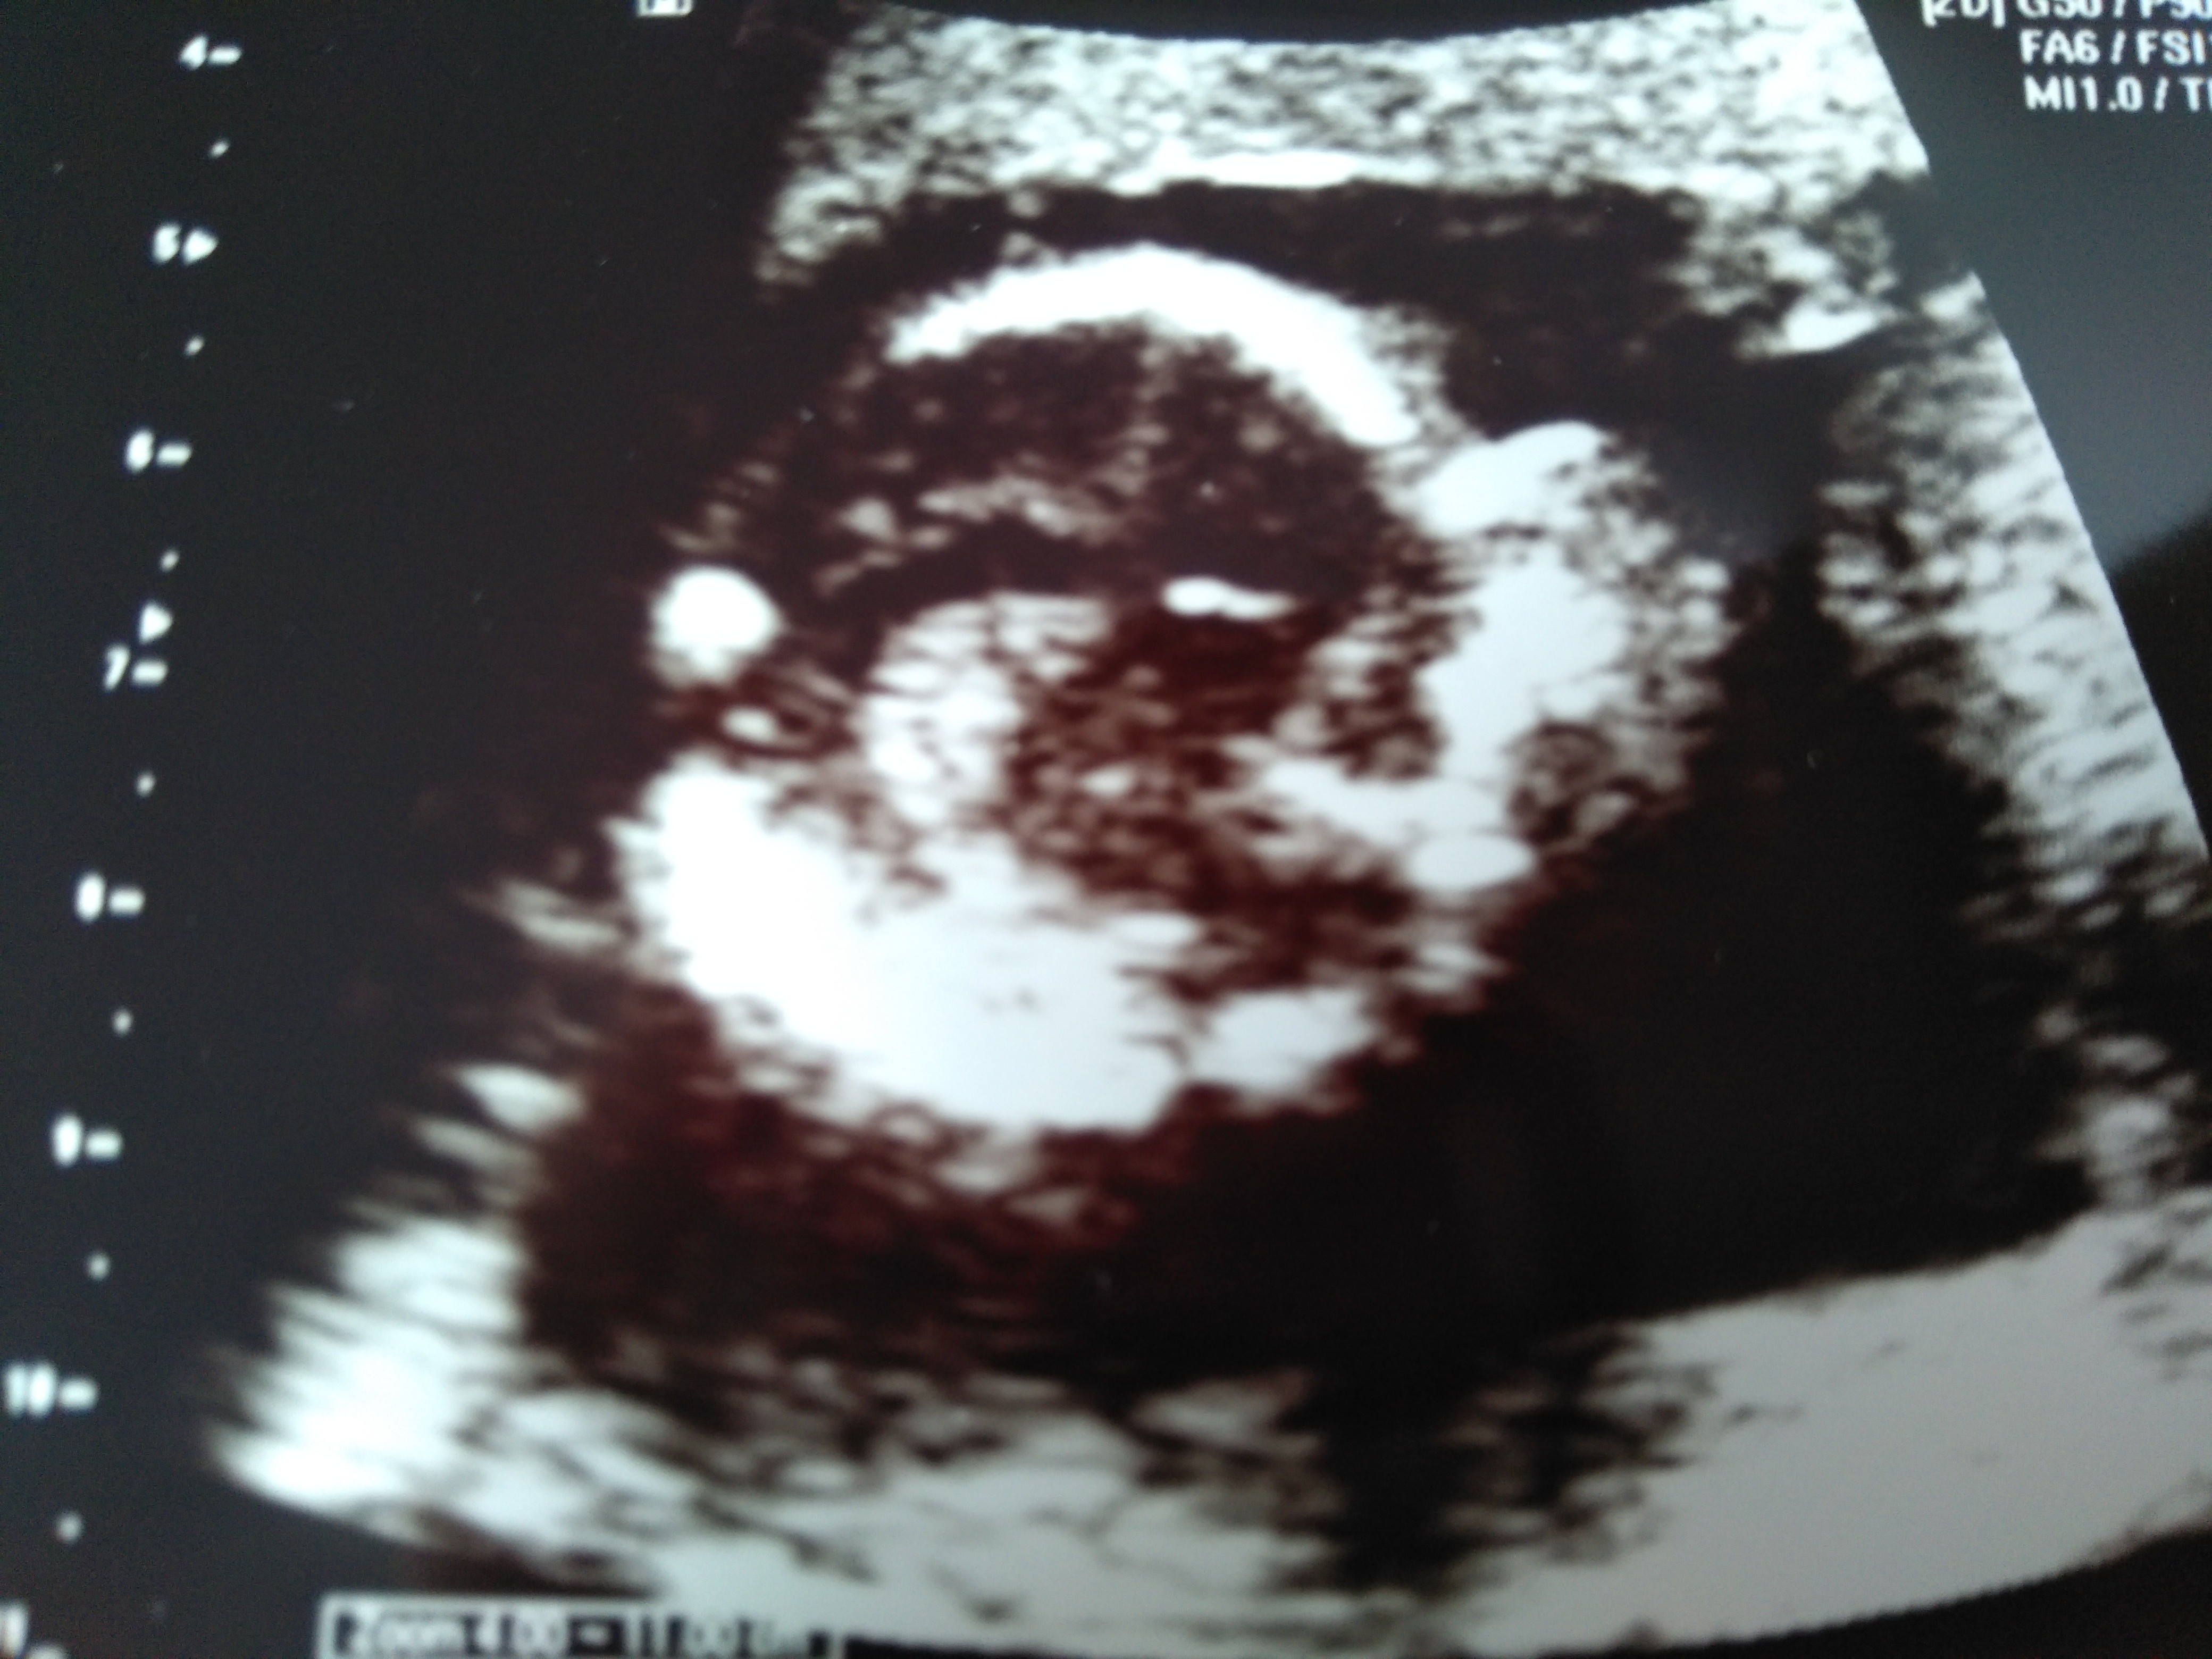

Oto mój Skarbuś

Załączniki

• IMG_20180825_133745.jpg

IMG_20180825_133745.jpg

1,8 MB · Wyświetleń: 147